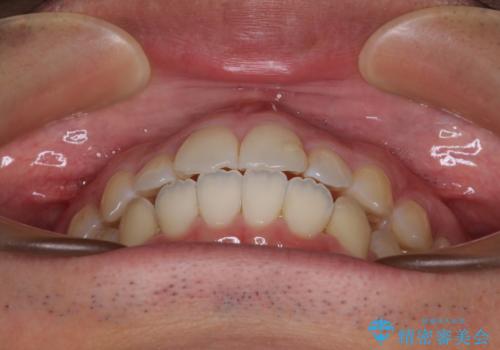

開咬とデコボコを整える インビザライン矯正治療

- 前歯の開咬と叢生を気にして来院された患者様です。

開咬の治療は、前歯を閉じるように動かすとともに、上下臼歯を圧下(骨内にめり込ませる)させることで進めて行きます。

インビザラインは臼歯の圧下を効果的に行えるため、インビザラインを用いて矯正治療を行うこととしました。また、アンカースクリューを用いて、口元の突出感の改善を図りました。